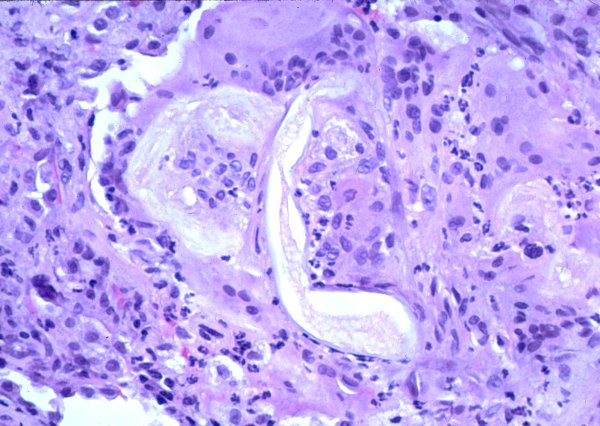

Кольцевидная гранулема – это хроническое доброкачественное заболевание кожи, клинически проявляющееся кольцевидно расположенными папулами (узелками), а патоморфологически – гранулематозным воспалением.

Клинические проявления. Мелкие плотные узелки, слегка возвышающиеся над уровнем кожи группируются в кольца или полукольца разной величины, чаще в виде множественных фигур. Центральная часть колец несколько западает. Элементы имеют цвет нормальной кожи, иногда с бледно-розовым, серовато-красным оттенком.

Преимущественная локализация — тыльная поверхность кистей и стоп, часто около суставов. У детей нередко наблюдается атипичная локализация — на лице, туловище, ягодицах. Очаги поражения могут быть как единичными, так и множественными. В некоторых случаях кожный процесс может носить распространенный и генерализованный характер. Кольцевидная гранулема обычно не имеет чешуек (шелушения) на поверхности и субъективно не беспокоит.

Кольцевидная гранулема может проявляться в виде подкожных очагов (чаще встречается у детей), представляющих собой плотные узлы, безболезненные при пальпации. Типичная локализация — передняя поверхность голеней, пальцы кистей и волосистая часть головы. Кожа над узлами не изменена.

Диагностика. Диагноз кольцевидной гранулемы обычно устанавливается на основании данных клинической картины, но может быть подтвержден при биопсии кожи.